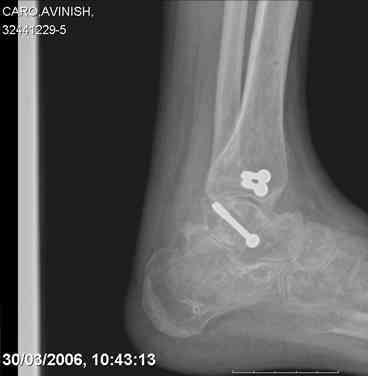

ya by popytalsya sobrat talus anatomichno,seichas pozdno operirovat iz za oteka,po etomy distrakziya apparatom budet optmalna.Posyalu vam podobyai moi sluchai.

14 years old girl

Fall from height ( 3rd floor)

Compressed fractures of L1-L2

Fx of orbital bone

Mark, судя по снимкам в день поступления произведен А.В.Ф., а остеосинтез ч-з какое время произведен?, остеосинтез произвели открытым способом?( на снимке п/о рубцы).

aparat postavlen v den postupleniya,rastaynuli, vpravili zakryto naskolko vozmoghno, a kogda otek spal sdelali otkrytoe vpravlenie.Teryat tut nechego, moghno tolko uluchshit.